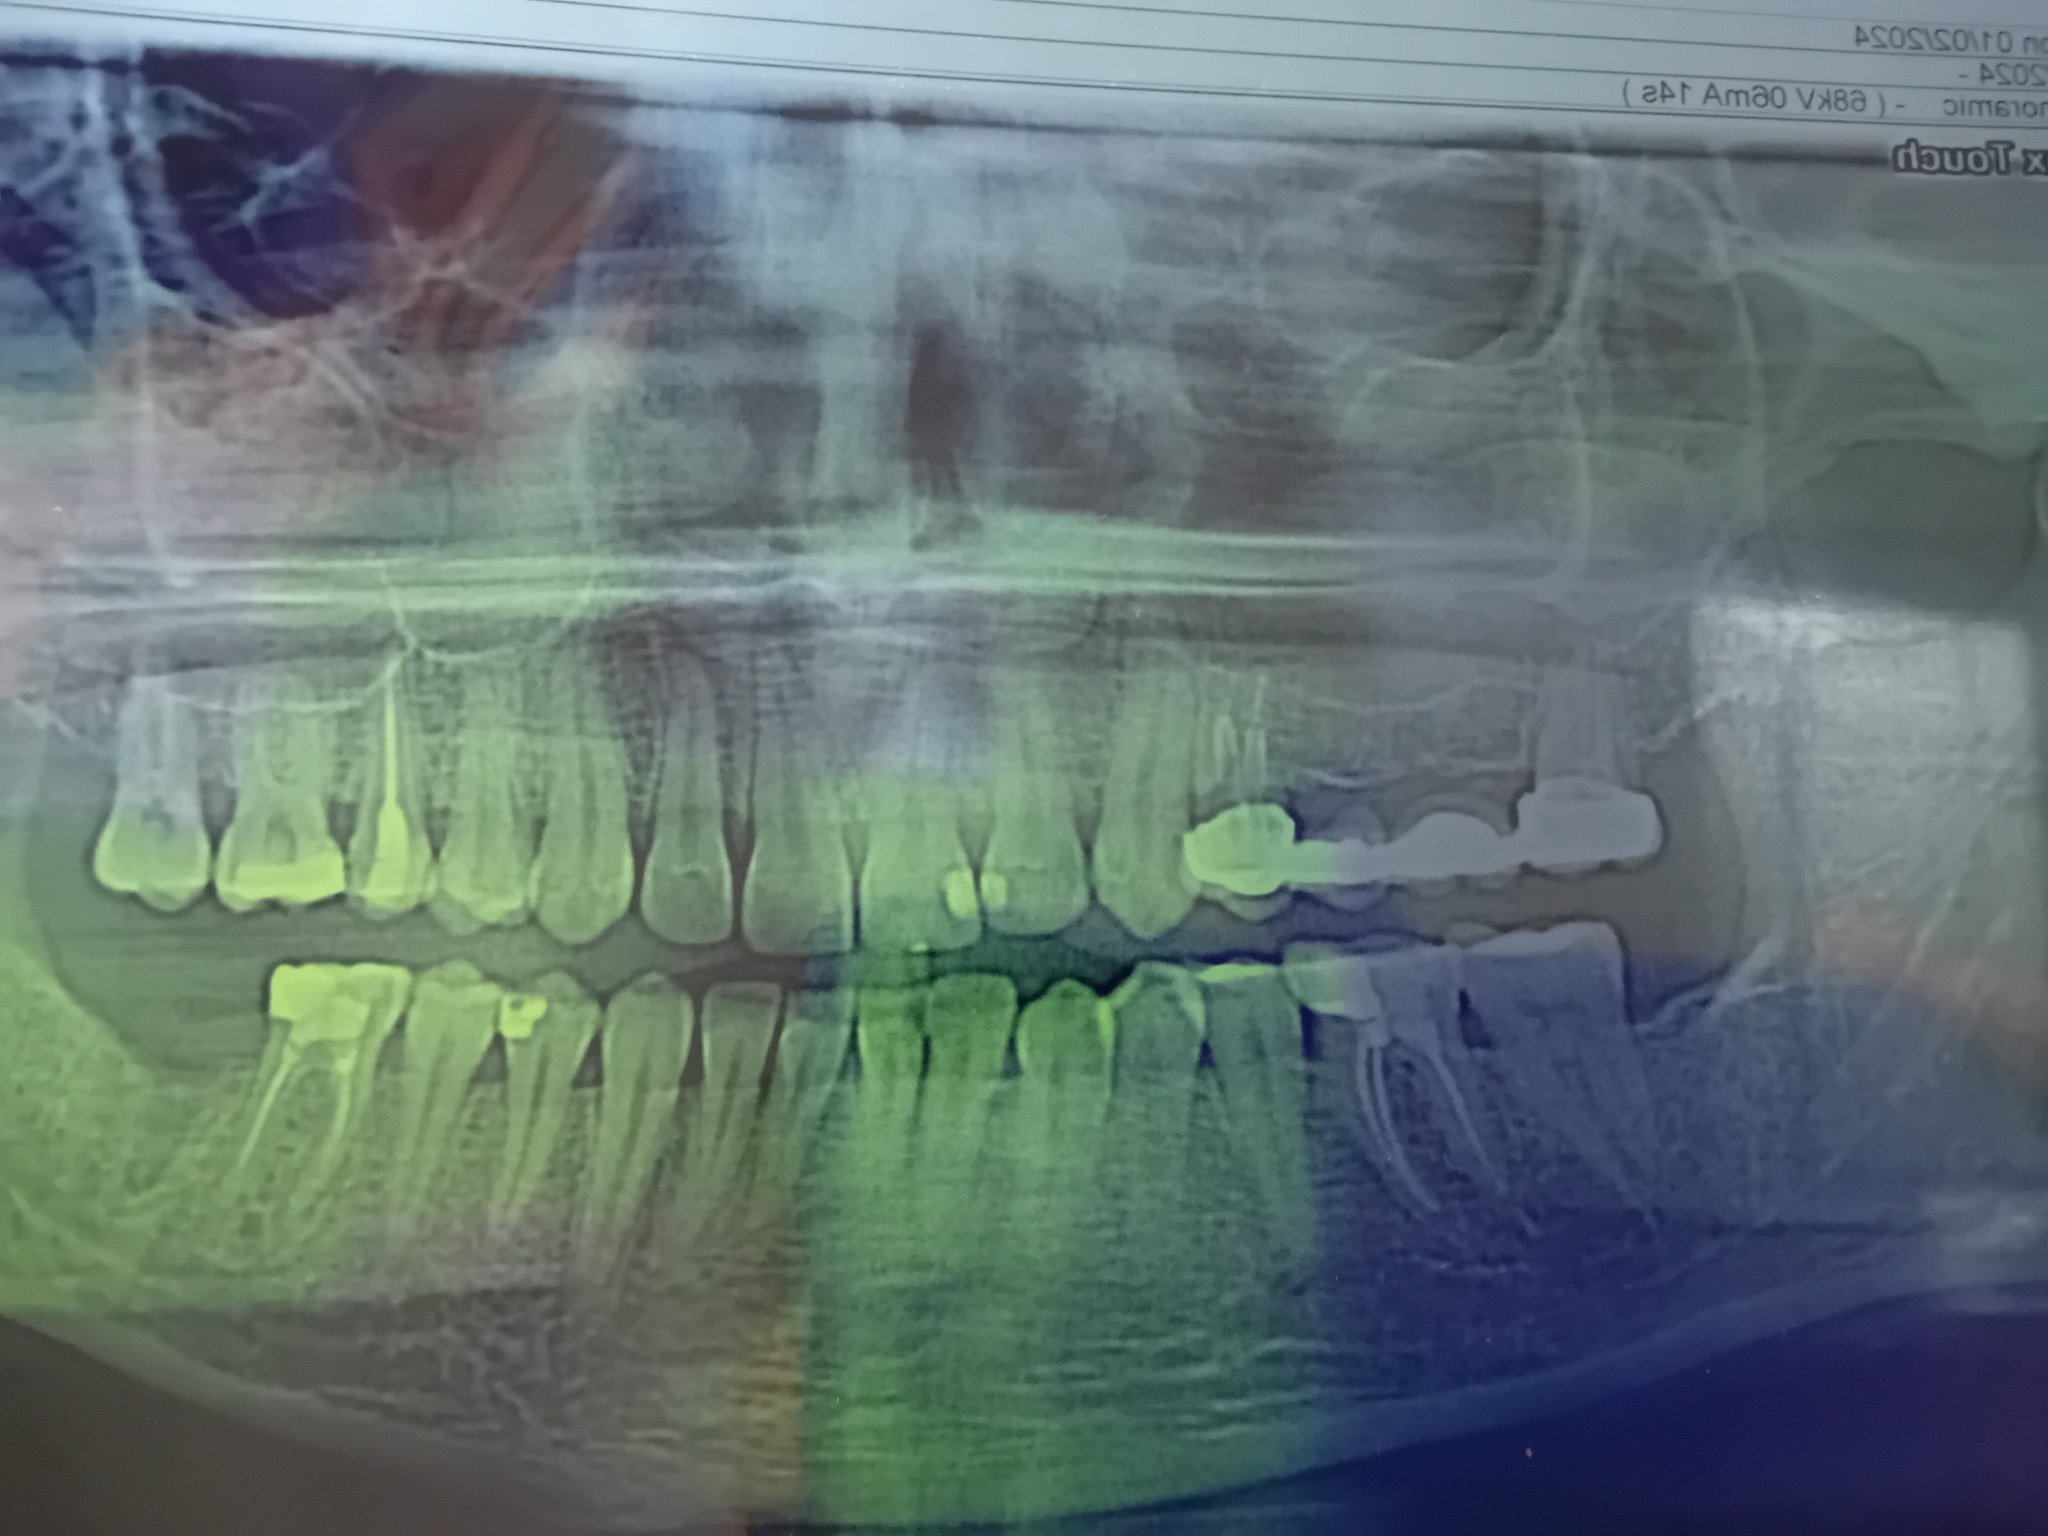

Постоянната болка след екстракция на нерв на зъб може да бъде причинена от неправилно лечение, неправилно кореново запълване или възпаление на кореновите канали. Обикновено болката трябва да намалее в рамките на 2-3 дни след процедурата. Ако болката продължава, препоръчително е да се консултирате със зъболекар.